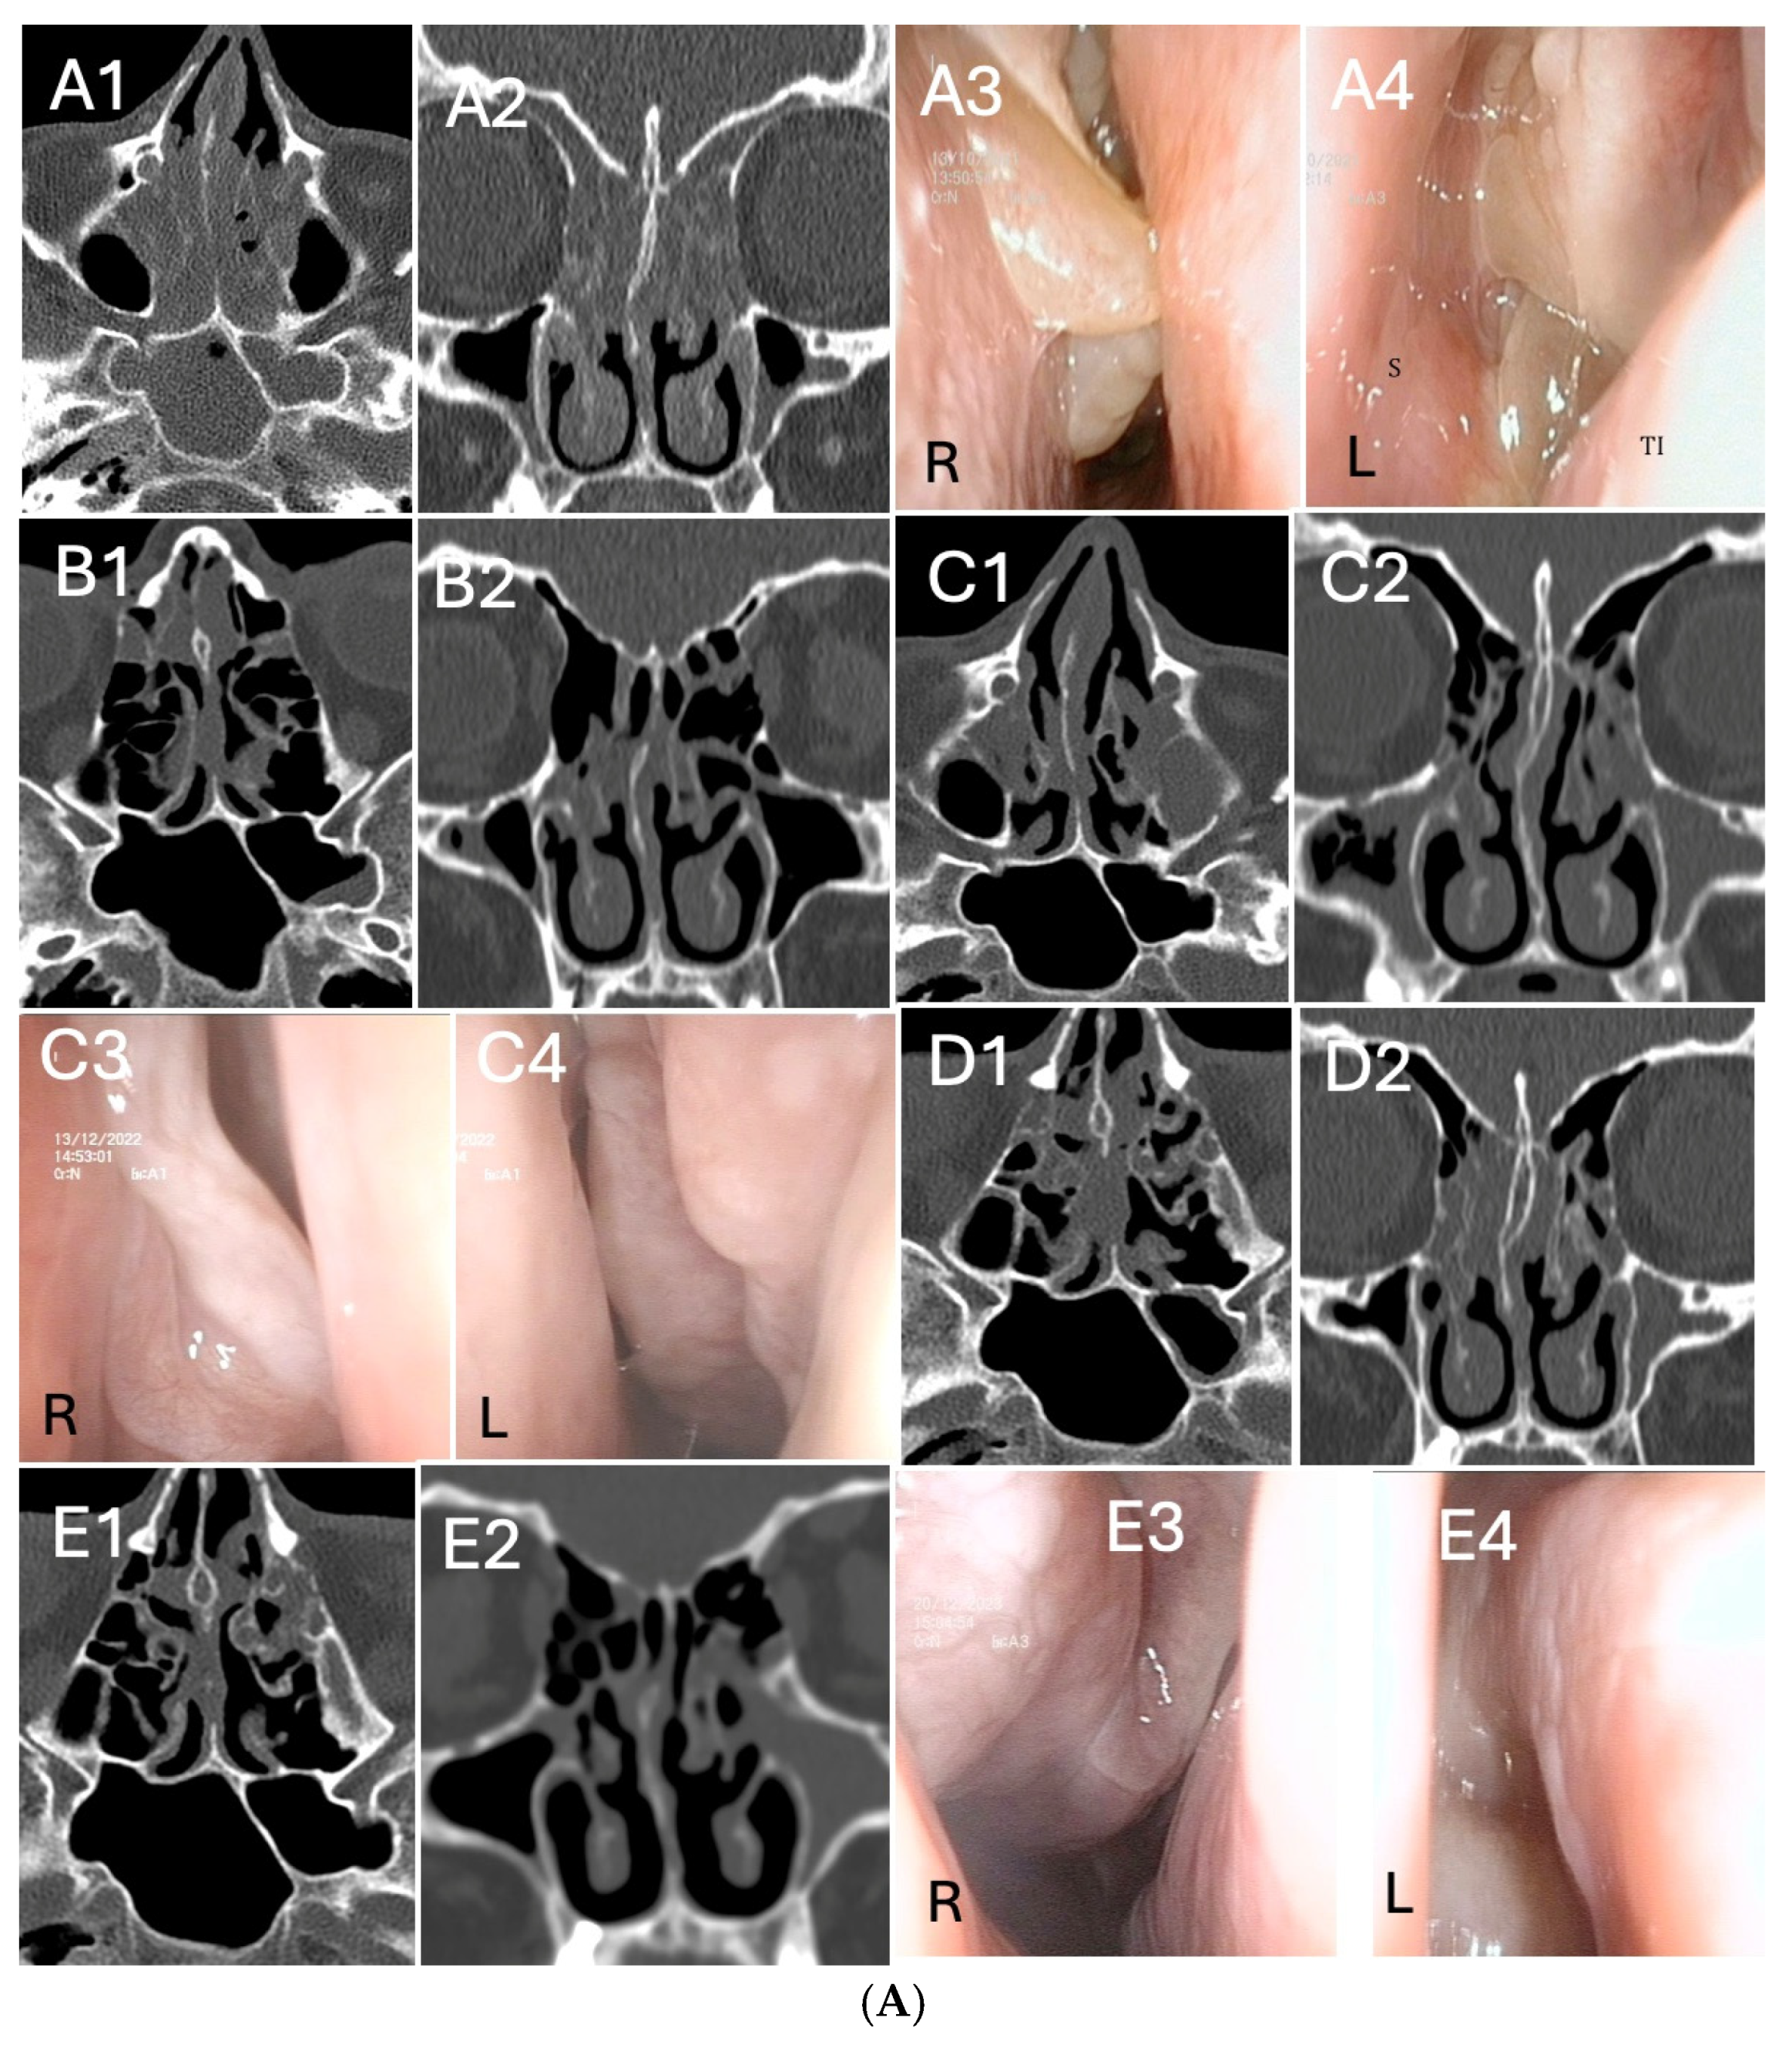

Three representative cases of radiologic and endoscopic outcomes before and after dupilumab treatment, according to basal Access Score and previous surgery, are reported in Figure 3A–C. Out of 32 patients, 2 underwent “adequate” Full House FESS of revision for relapsing CRSwNP during dupilumab treatment (one reported in Figure 3B).

Figure 3.

(A). Radiological and endoscopic (R = right, L = left) images in relation to dupilumab therapy without surgery in CRSwNP (eosinophils>30/hpf). (A1–A4): start of dupilumab. Axial (A1) and coronal (A2) computed tomography (CT) images show pansinusitis. Endoscopic examination (A3,A4) of both nasal cavities shows polypoid formation completely occupying the nasal fossa (total NPS = 7) S:sinus; TI:turbinate. (B1,B2): 6 months after initiation of dupilumab. Sphenoidal (B1), frontal and maxillary sinuses (B2) completely disease-free. Pictures (C1–C4): 12 months after initiation of dupilumab. Radiologic (C1,C2) and endoscopic examination (C3,C4) of both nasal cavities show significant reduction of polypoid mass. (D1,D2): axial (D1) and coronal (D2) computed tomography (CT) images 18 months after initiation of dupilumab. Outcomes are maintained in the long run. (E1–E4): 24 months after initiation of dupilumab. Maintenance of the radiological (E1,E2) and endoscopic (E3,E4) outcomes is evident, even at long term follow-up visit. (B). Radiological and endoscopic (R = right, L =left) images in relation to dupilumab therapy after “adequate” Full House FESS of revision for CRSwNP. (A1–A4): CT (A1,A2) and MRI (A3,A4) images showing CRSwNP recurrence after two “not adequate” FESS (ACCESS score 20/24). Intra-operatory images (RESS): (A5) right nasal fossa NPS = 4; (A6) debridement of nasal polyps; (A7) left maxillary sinus empyema; (A8) frontal sinusotomy. (B1–B4): start of dupilumab 18 months after “adequate” Full House FESS, following CRSwNP relapse (eosinophils>50/hpf). Endoscopic (B1,B2) and radiological (B3,B4) images, ACCESS score 2/24. (C): 6 months after initiation of dupilumab. Radiologic (C1,C2) and endoscopic examination (C3,C4) of both nasal cavities shows partial reduction of polypoid mass. (D1–D4): 12 months after initiation of dupilumab, a local control of the disease is evidenced in both axial (D1) and coronal (D2) computed tomography (CT) and endoscopic (D3,D4) images (E1–E4): 24 months after initiation of dupilumab, images highlight the maintenance of the radiological (E1,E2) and endoscopic (E3,E4) results even at long term follow-up visits. Inferior turbinates are preserved, while middle turbinate was remodeled for correct sinus ventilation and disease control. “ss”: sphenoid sinus; “sm”: maxillary sinus. (C). Radiological and endoscopic (R = right, L = left) images in relation to dupilumab therapy after “adequate” salvage Full House FESS in patient who underwent two previous “not adequate” surgeries (last surgery performed 18 months before starting dupilumab). (A1–A4): The patient started biologic treatment with dupilumab. Coronal (A1) and axial (A2) CT scans evidenced ethmoidal cells still not opened and hyperostosis of the anterior and posterior compartment. Endoscopic images (A3,A4): NP relapse and tissue remodeling. (B1–B4): 6 months after initiation of dupilumab, persistence of nasal polyps seen radiologically (B1,B2) and endoscopically (B3,B4). (C1–C4): 18 months after initiation of dupilumab, ACCESS score 22/24 (C1,C2). Endoscopic sinus surgery (C3,C4) was performed in this patient, keeping on treatment with dupilumab. (D1–D4): 1 year after “adequate” Full House FESS and 3 years after dupilumab. TC scans (D1,D2) evidenced paranasal sinuses fully opened. Corresponding endoscopic image (D3,D4).